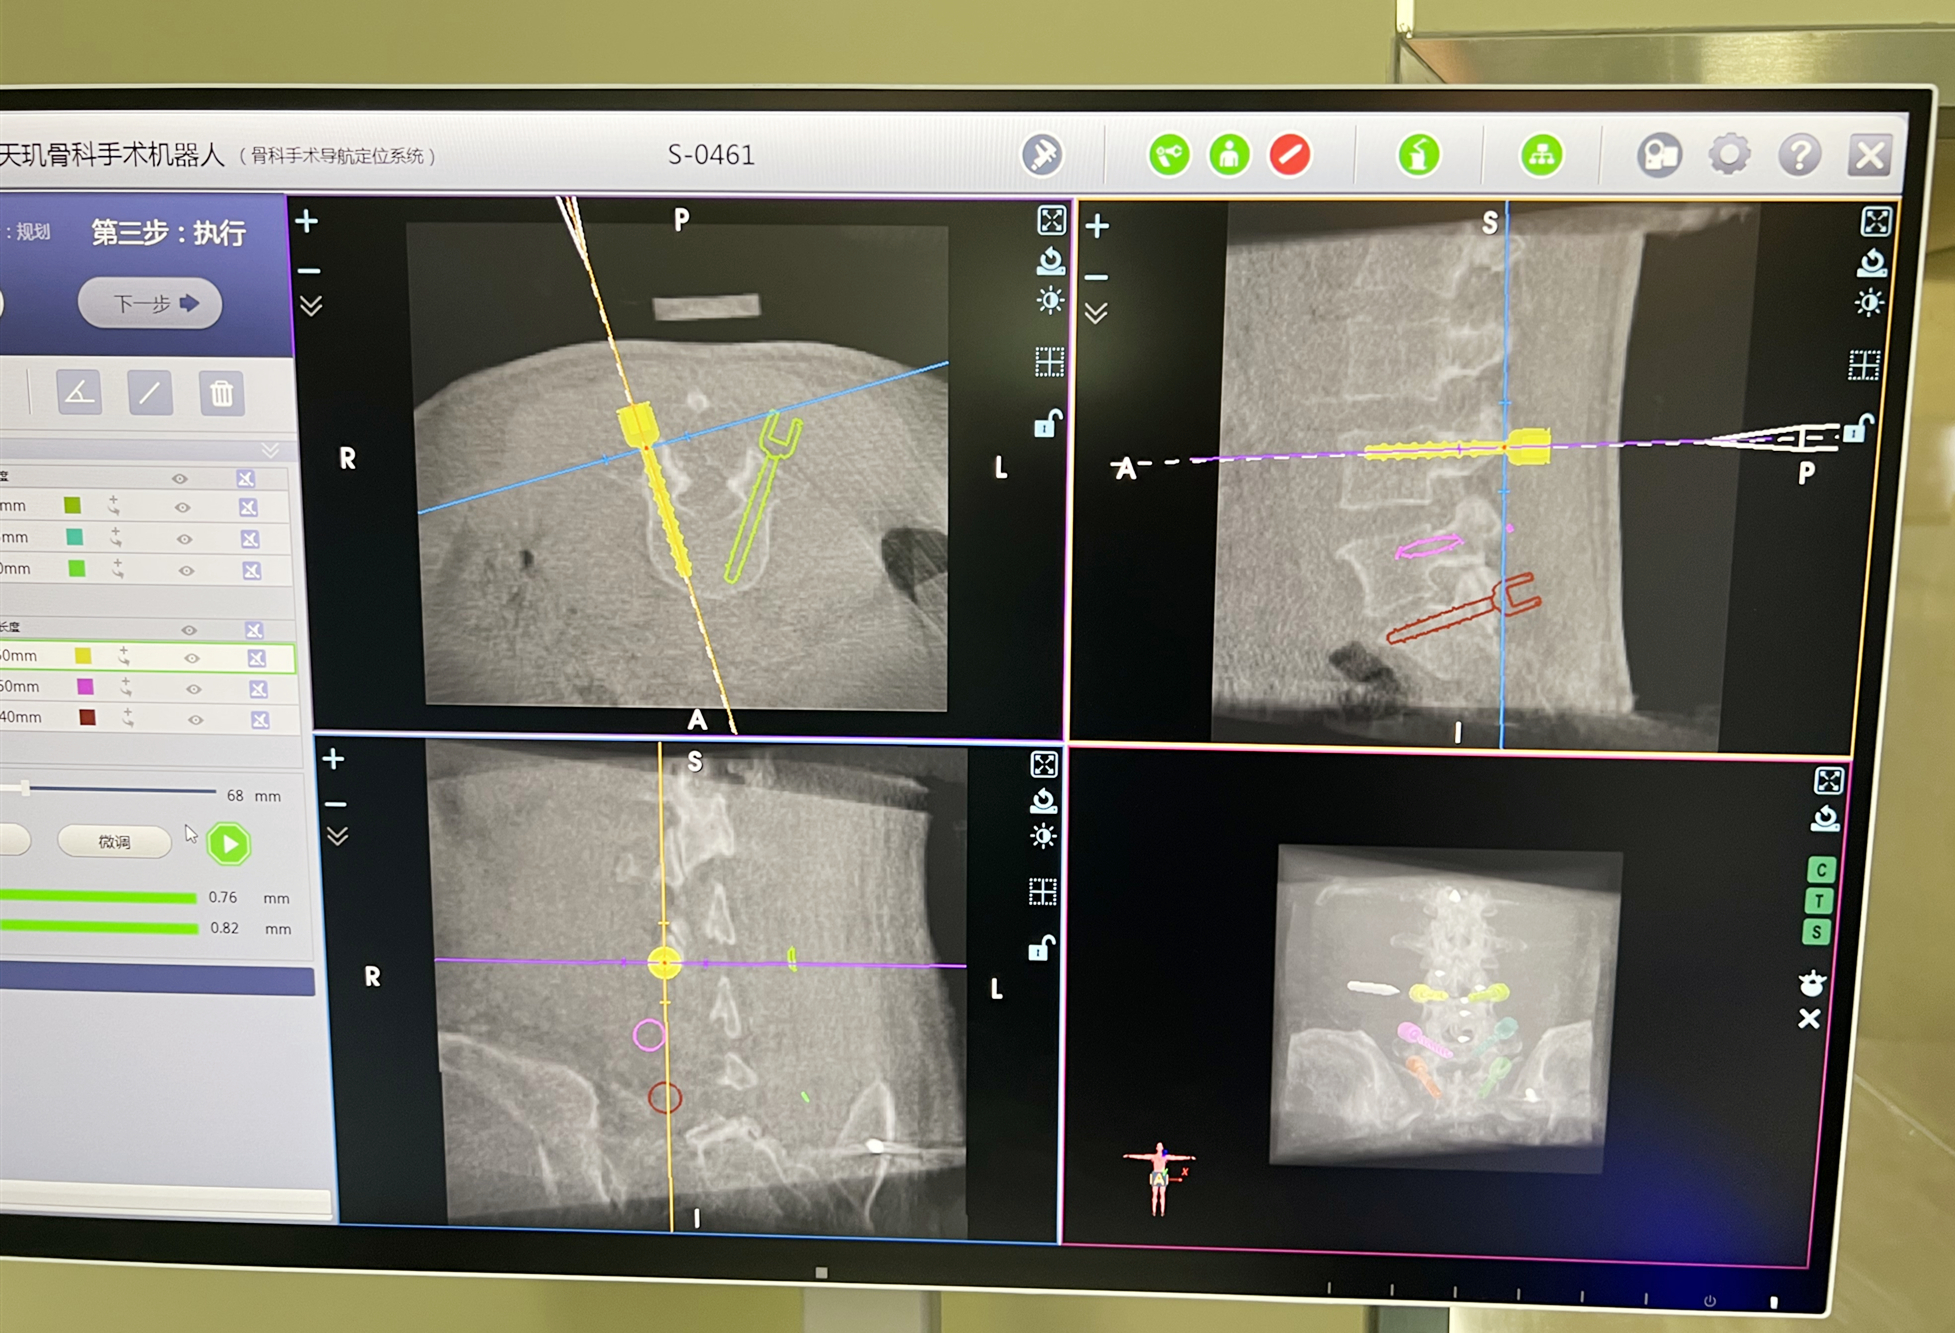

在骨科手术机器人的辅助下,通过术中3D影像图像进行精准置钉路径定位规划,手术团队结合既往开放手术的经验,顺利在椎弓根置钉通道完成精准置钉,螺钉及走行位置满意,然后再行融合技术。术后患者症状得到有效缓解。借助天玑III骨科手术机器人的辅助,精准、高效地完成了手术,手术出血不到150ml,术后生命体征平稳,双下肢感觉、运动正常,脊柱序列恢复满意。

天玑III骨科手术机器人辅助下置钉

“天玑”骨科手术机器人能够辅助开展脊柱外科手术以及创伤骨科手术,可通过机械臂辅助完成术中手术器械或植入物的定位。其兼容2D与3D模式,独有入钉点及钉道计算智能算法,能使机械臂精准运动到规划位置,从而借助骨科引导器,为医生提供精准稳定的导针置入路径。按照术中规划,医生可以精准设计并置入内植入物。天玑骨科机器人另辟蹊径,使常规手术精准微创化、复杂手术标准化、关键操作智能化、医疗资源均等化,具有显著临床优势,更加智慧的骨科手术,未来可期。